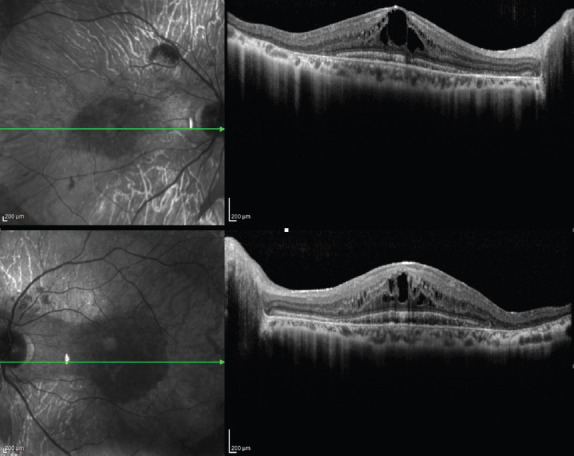

Gyrate atrophy (GA) is a hereditary condition characterized by ornithine aminotransferase deficiency-related large areas of retinal pigment epithelium and choriocapillaris lobular-shaped atrophy in the peripheral retina. In this report, we present a case of atypical presentation of GA. The aim of this report is to present two siblings, one of which was associated with a lamellar macular hole and with a history of previous diagnosis of retinitis pigmentosa. The delayed diagnosis of GA was made only after her brother, who was 5 years younger than her was diagnosed with GA. In addition, in this report, we evaluated GA in terms of multimodal imaging findings, differential diagnosis, and treatment of macular complications.